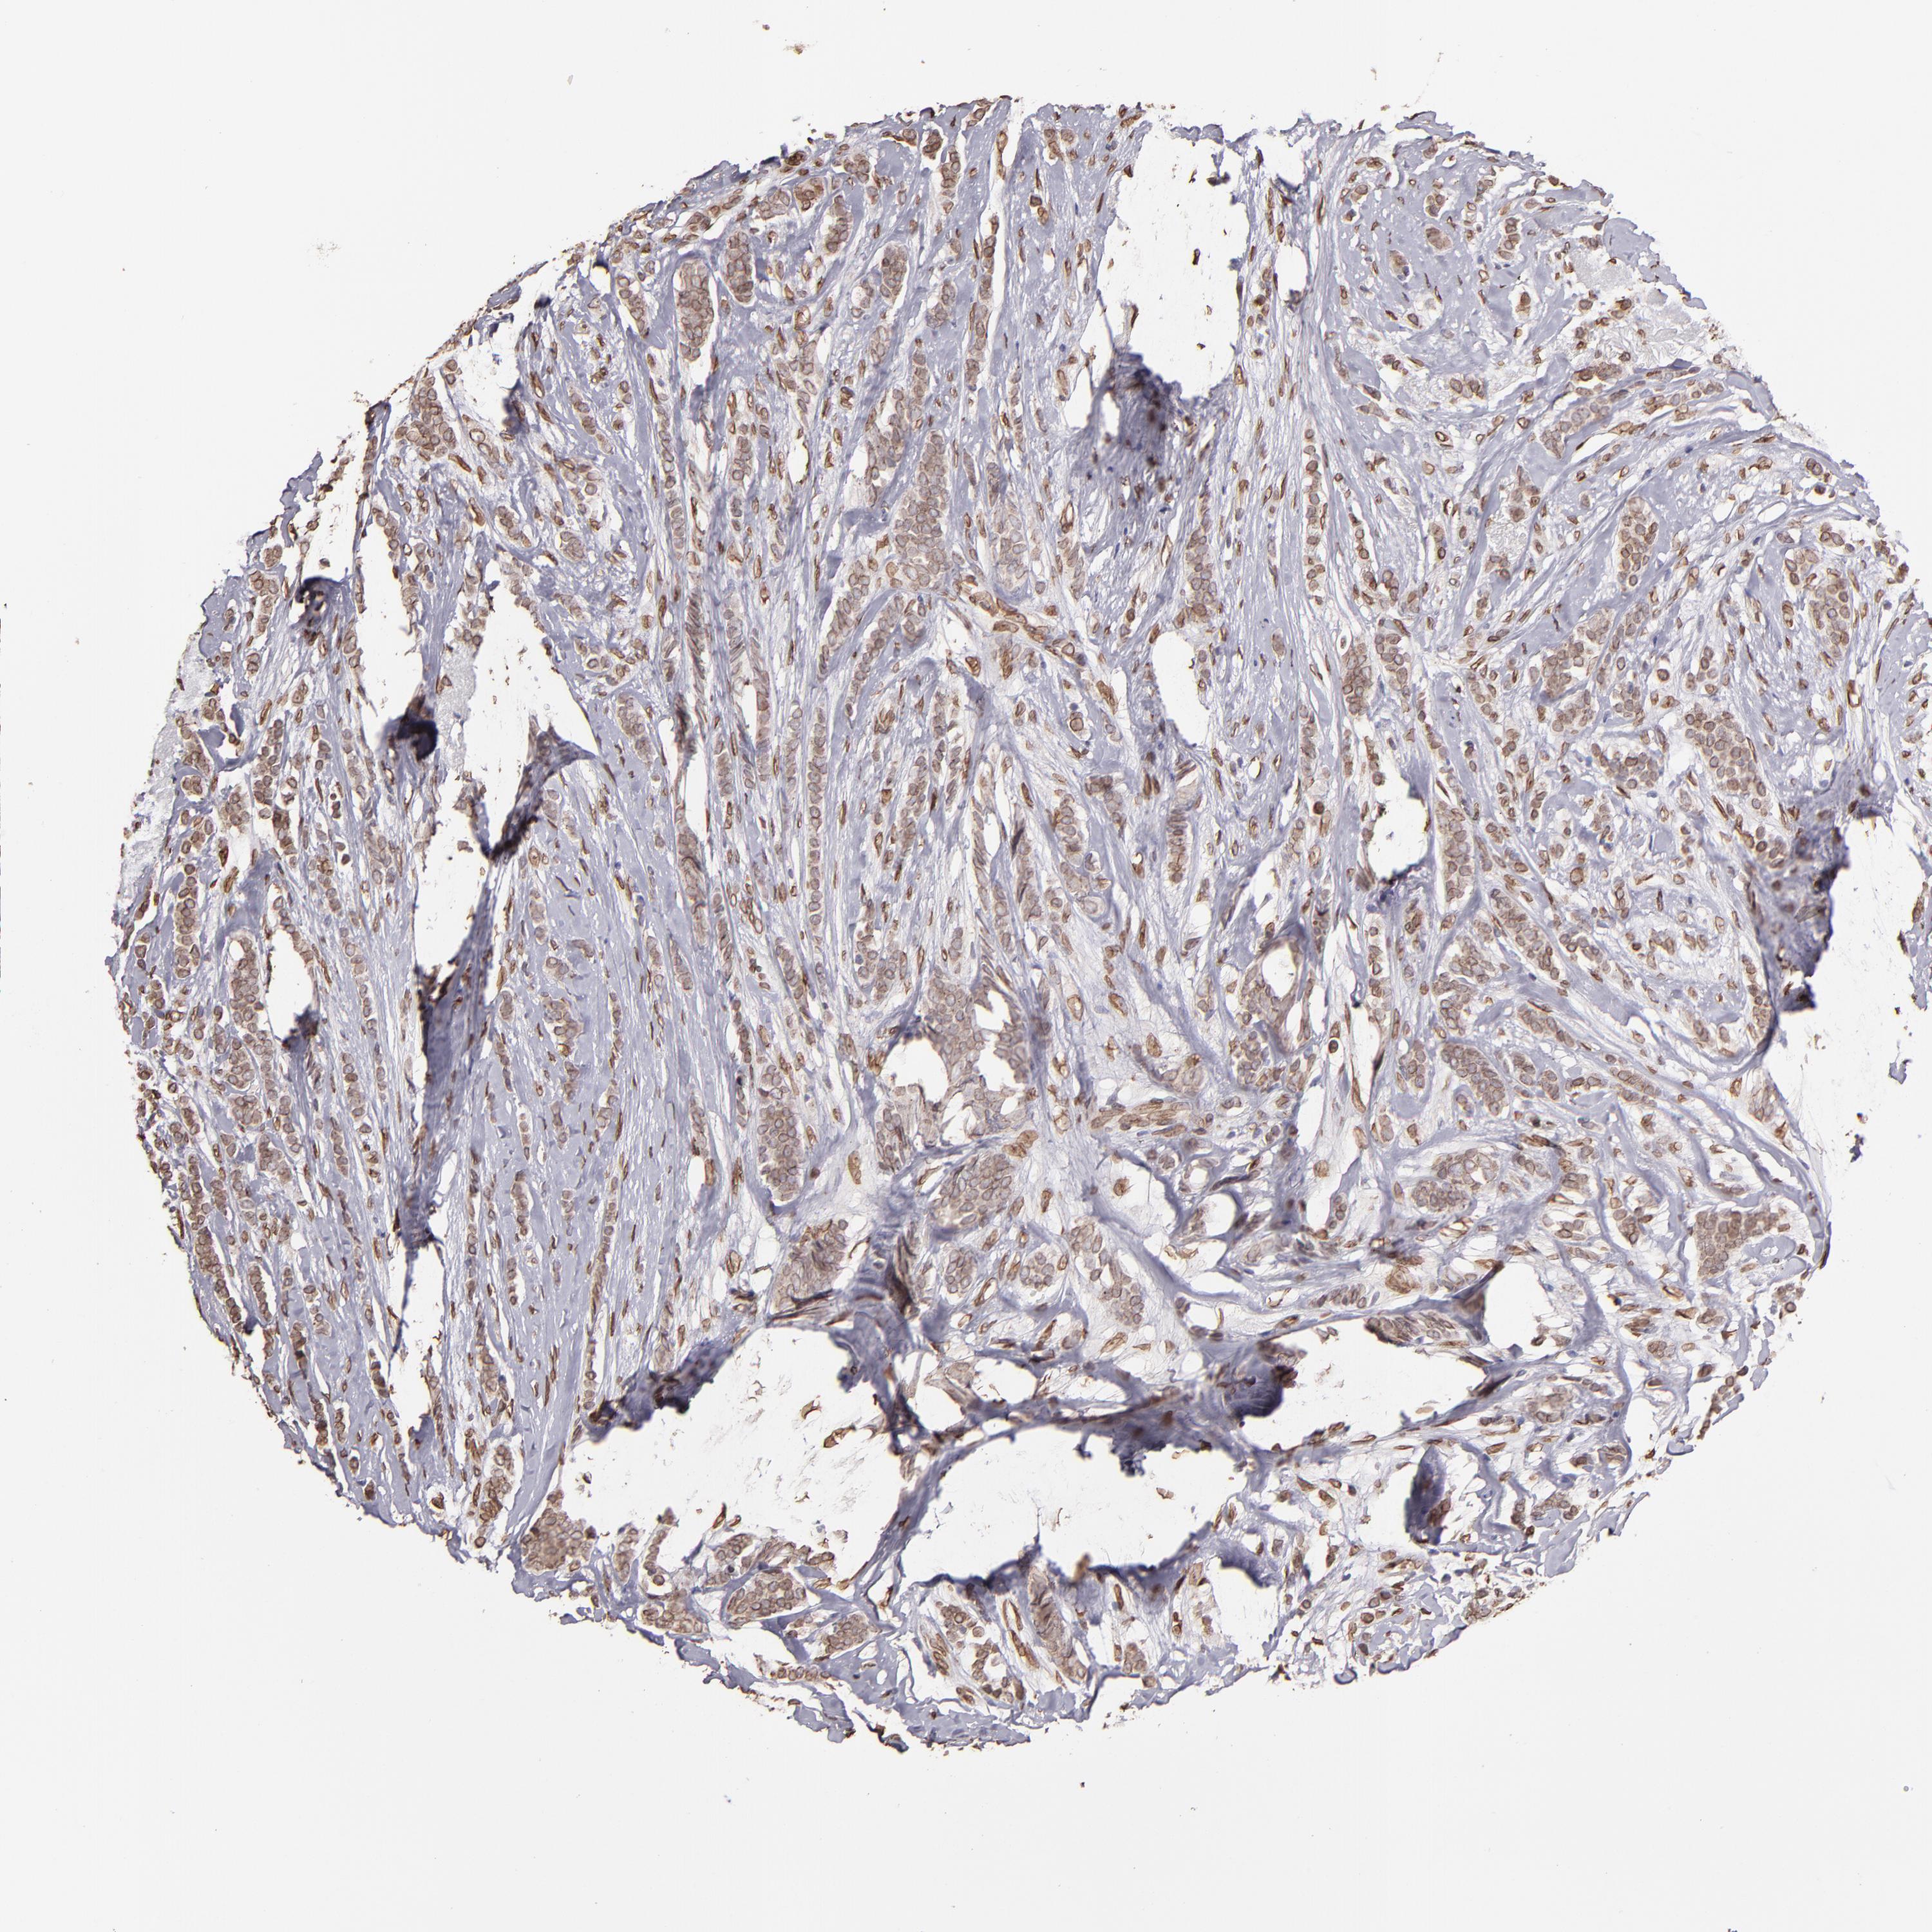

CANCER BREAST CANCER Show tissue menu

Breast cancer

Human cancer